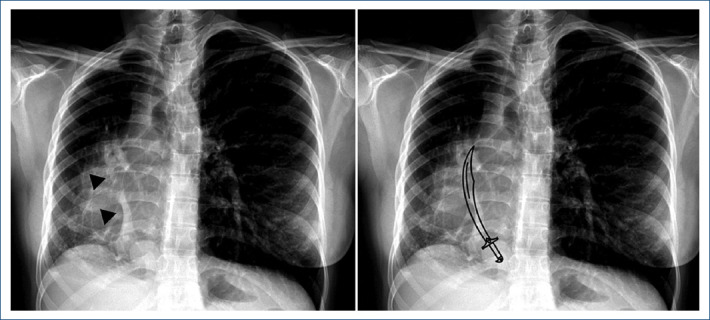

The Ottoman empire sword: a variant of partial anomalous pulmonary veins connections.

{"title":"The Ottoman empire sword: a variant of partial anomalous pulmonary veins connections.","authors":"Karla A Pupiales-Dávila, Vincenzo Arenas-Fabbri, Edgar García-Cruz, Pamela Ramirez-Rangel","doi":"10.24875/ACM.24000029","DOIUrl":null,"url":null,"abstract":"","PeriodicalId":93885,"journal":{"name":"Archivos de cardiologia de Mexico","volume":" ","pages":"122-125"},"PeriodicalIF":0.0000,"publicationDate":"2024-07-29","publicationTypes":"Journal Article","fieldsOfStudy":null,"isOpenAccess":false,"openAccessPdf":"https://www.ncbi.nlm.nih.gov/pmc/articles/PMC12148509/pdf/","citationCount":"0","resultStr":null,"platform":"Semanticscholar","paperid":null,"PeriodicalName":"Archivos de cardiologia de Mexico","FirstCategoryId":"1085","ListUrlMain":"https://doi.org/10.24875/ACM.24000029","RegionNum":0,"RegionCategory":null,"ArticlePicture":[],"TitleCN":null,"AbstractTextCN":null,"PMCID":null,"EPubDate":"","PubModel":"","JCR":"","JCRName":"","Score":null,"Total":0}